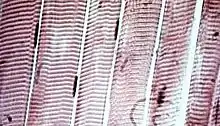

Striated skeletal muscle cells in microscopic view. The myofibers are the straight vertical bands; the horizontal striations (lighter and darker bands) that are a visible result from differences in composition and density along the fibrils within the cells. The cigar-like dark patches beside the myofibers are muscle-cell nuclei.